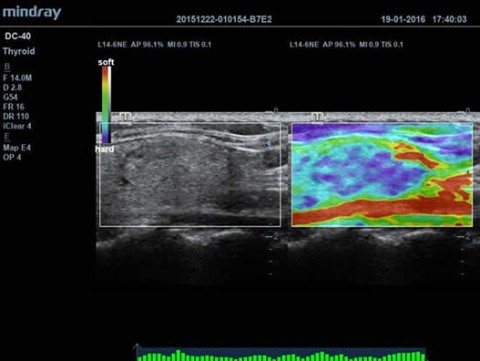

Встроенная батарея, Сенсорный экран, Эластография, 4D модуль, CW доплер